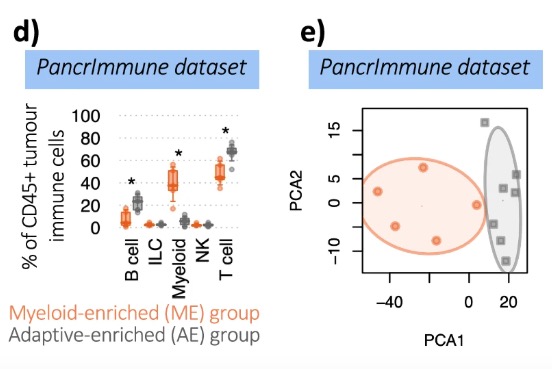

Distinct immune cell infiltration patterns in pancreatic ductal adenocarcinoma (PDAC) exhibit divergent immune cell selection and immunosuppressive mechanisms

doi:10.1038/s41467-024-55424-2

Single-cell immune multi-omics and repertoire analyses in pancreatic ductal adenocarcinoma reveal differential immunosuppressive mechanisms within different tumour microenvironments

doi:10.1101/2023.08.31.555730